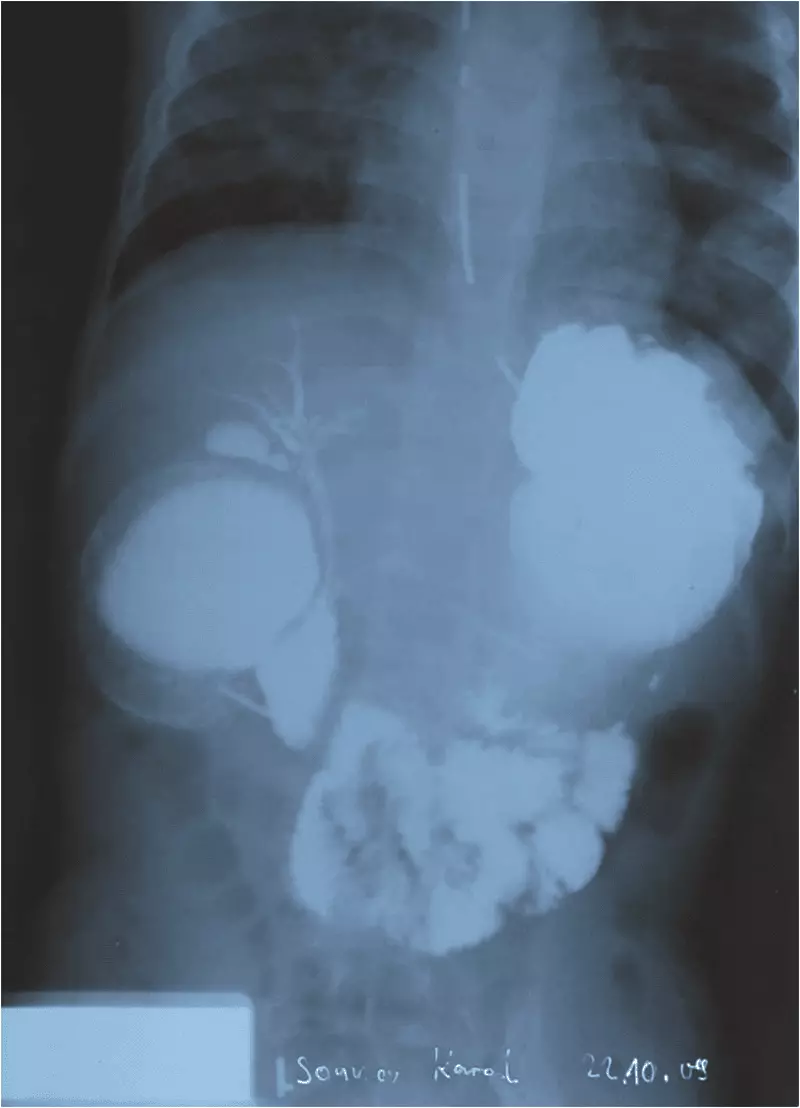

Wiążąc incydent zachłyśnięcia oraz obserwowane od okresu niemowlęcego ulewania, wymioty i trudności w karmieniu z utrudnieniem pasażu treści pokarmowej, po ustąpieniu u chłopca objawów infekcji, wykonano pasaż górnego odcinka przewodu pokarmowego. Kontrast barytowy podano przez sondę umieszczoną w okolicy przedodźwiernikowej żołądka. Po podaniu kontrastu uzyskano wsteczne wypełnienie się żołądka oraz fragmentu poszerzonej dwunastnicy. Żołądek poszerzony był rozstrzeniowo, o znacznie pogrubiałych fałdach błony śluzowej, znacznie poszerzony był też odcinek dwunastnicy sięgający do brodawki Vatera. Od wysokości brodawki Vatera uwidoczniono natomiast zwężenie dwunastnicy obejmujące prawie całość jej części zstępującej. Po 10 minutach kontrast obecny był w jelicie czczym i krętym, ale pasaż kontrastu utrudniony. Zaleganie kontrastu w żołądku i poszerzonej części dwunastnicy utrzymywało się do końca badania – ok. 45 minut. W początkowej fazie badania, podczas przechodzenia kontrastu do jelita czczego, zakontrastowaniu uległy też drogi żółciowe wraz z pęcherzykiem żółciowym oraz przewód Wirsunga, wykazywały one mierne poszerzenie (ryc. 1).

Ryc. 1. Pasaż przewodu a (opis w tekście powyżej)